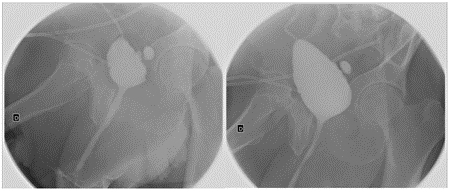

The patient presented a satisfactory postoperative period, being able to remove the urinary catheter and suprapubic catheter at 3 weeks (Figure 11), achieving spontaneous urination without involuntary leakage of urine due to the preservation of the internal urinary sphincter (bladder neck). After the removal of the bladder catheter, a cystography was performed showing a good urethral caliber without contrast leakage (Figure 12).

Figure 12: Urethrogram showing a small-capacity multidiverticular bladder and a good-caliber urethra without contrast leakage.